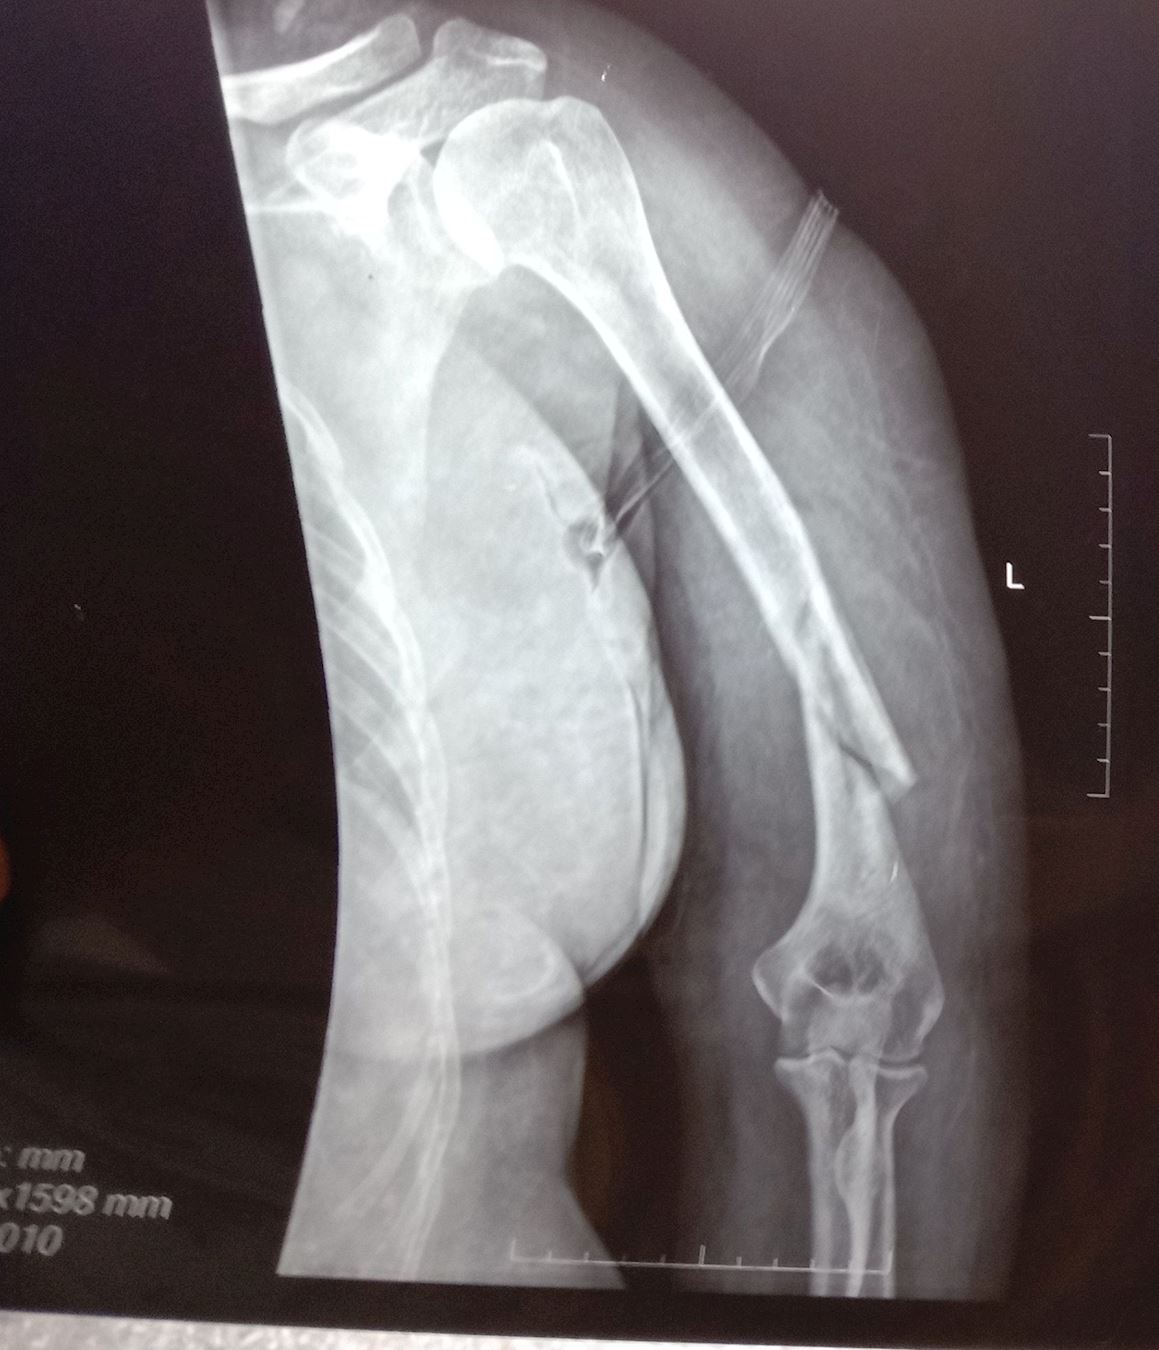

'高翠莲的胳膊被警察扭断'

高翠莲的胳膊被警察扭断

1、被警察把左手臂扭断

2014年4月21日,公婆把高翠莲送到石林县人民医院,检查被警察打伤不能动的胳膊。拍片子检查结果是;螺旋式粉碎性骨折。医生说,要马上住院,进行手术治疗。家人身上没有那么多钱,只好回家。

2014年4月23日,家人把高翠莲送到昆明市43医院住院治疗,检查结果;螺旋式粉碎性骨折。由于费用太高,还没有做手术,就没有多少钱了,只做了伤情鉴定书,就回家了。

2014年4月26日,伏培生从看守所回到家,又把妻子高翠莲送到石林县天奇医院,检查结果;螺旋式粉碎性骨折。主治医生陈伟告诉高翠莲:政府部门的人员找过他了,你只要承认自己的手臂是不小心摔断的,就可以报销医疗费。高翠莲告诉医生:不说假话,我的手臂就是被警察扭断的。虽然家里困难,家人决定自己凑钱给高翠莲做手术。手术前几天,几个专家来问高翠莲的身体情况,结果发现高翠莲的身体对金属过敏,对针水也过敏,无法治疗,要求转院治疗。家人没有办法,只好回家。